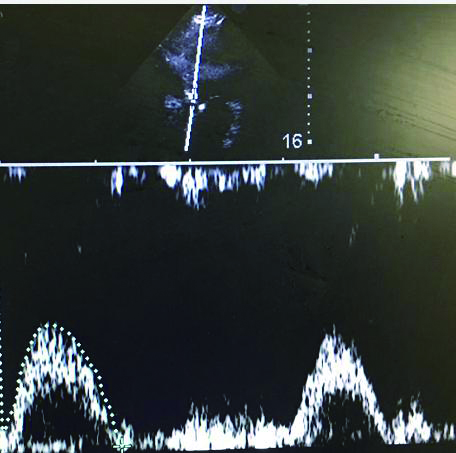

充分暴露前胸部,于胸骨旁长轴切面,选取主动脉瓣根部测量左室流出道直径与截面积。选取心尖五腔心切面,通过脉冲多普勒测量动脉流速,计算左心室流出道收缩高峰期的流速时间指数,测量心率,最后通过心脏检查软件包自动计算出CO(图 3、4)。通过上述PLR试验,联合超声获得的CO,最后计算ΔCO值,ΔCO≥15%定义为容量反应性阳性;反之为容量反应性阴性。

|

| 图 4 心尖部五腔心流速时间指数测量 Figure 4 The measurement of apical velocity time index at five-cavity flow |

|

|